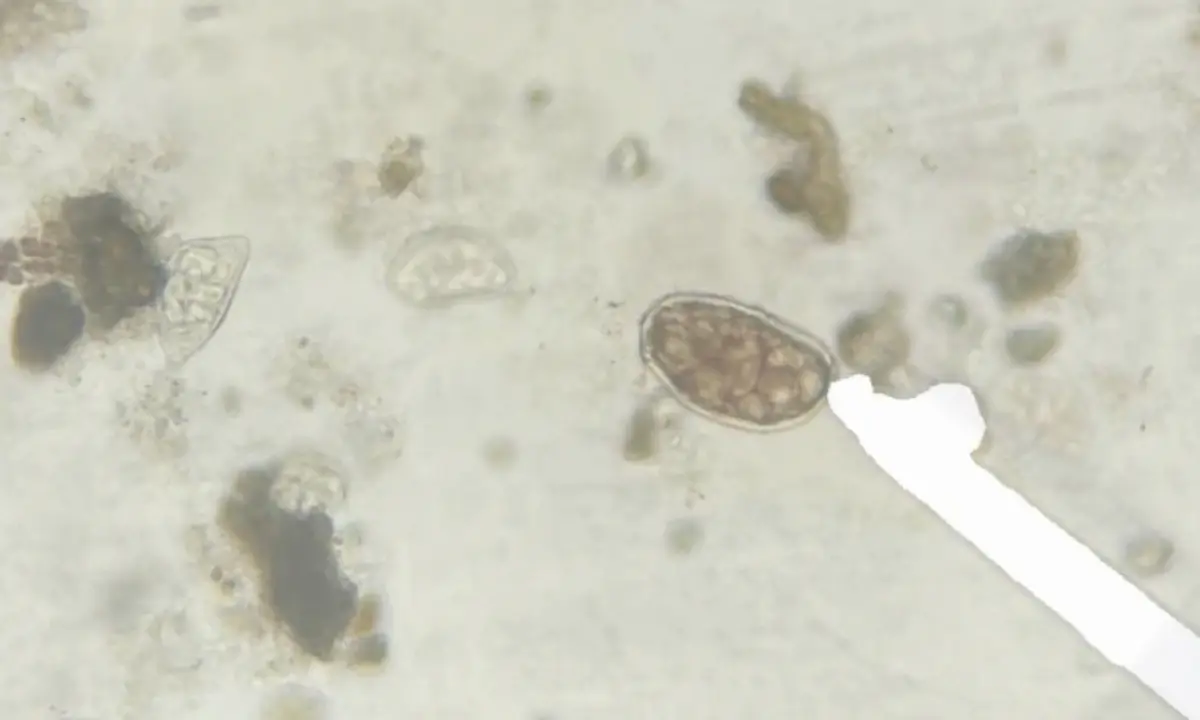

Parasitologia Digital: Diagnóstico Veterinário Automatizado

Sistema de visão computacional aplicado à medicina veterinária para detecção automática de parasitas e ovos em exames coproparasitológicos de animais domésticos. Inclui pré-processamento de imagens microscópicas e análise estatística de correlações climáticas.

MicroscopiaVeterináriaSaúde Animal